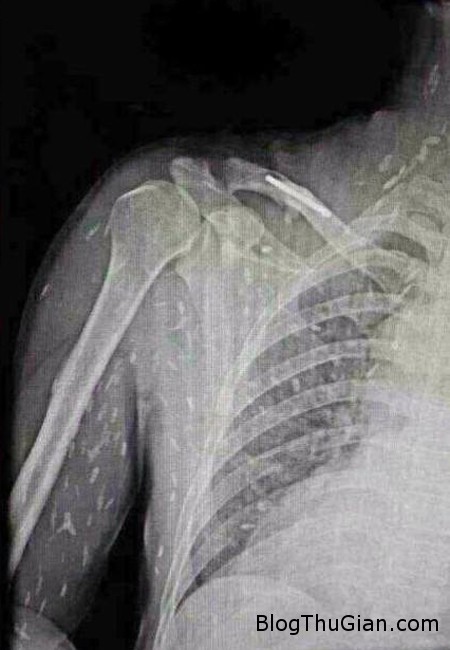

Tuy nhiên, do bệnh tình đã bước sang giai đoạn nghiêm trọng nên người đàn ông tiếp tục được chuyển tới Bệnh viện Nhân dân số 8 ở Quảng Châu để điều trị. Kết quả chụp X-quang cho thấy, những đốm trắng nhỏ xuất hiện lấm chấm khắp cơ thể chính là sán.

Những chấm trắng xuất hiện trên hình chụp X-quang là sán.